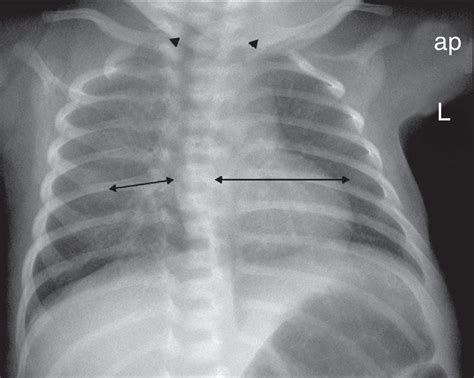

Tras ser trasladado a la unidad de cuidados neonatales para seguimiento y valoración clínica, a las 12 horas posparto, el neonato presentó un cuadro clínico caracterizado por llanto incontrolable e irritabilidad, que se exacerbaba con la movilización. Además, se observaron episodios de rechazo de la vía oral y desaturación. Los estudios complementarios realizados incluyeron una radiografía de tórax, la cual reveló fracturas costales izquierdas en el quinto y sexto arcos costales. El resto de los parámetros paraclínicos se encontraron dentro de los rangos normales.

tags: #fracturas #costales #radiografia #neonato